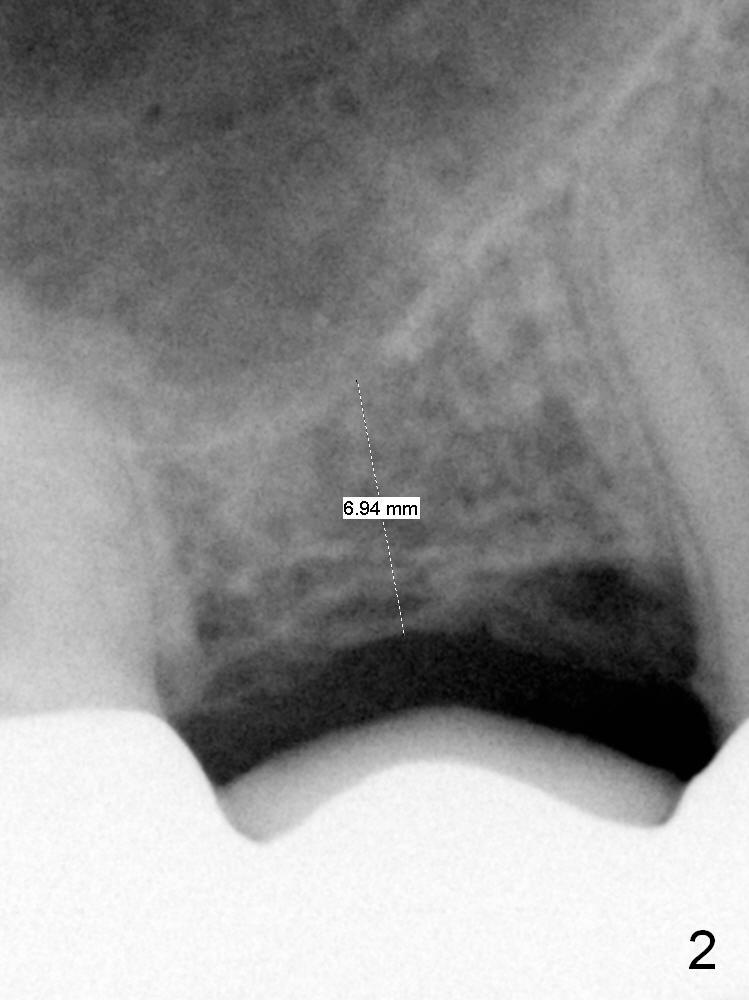

A 63-year-old man complains of loose bridge in the upper right quadrant. There is open margin at #4 (Fig.1). After sectioning between #2 and 3 without anesthesia, explore the tooth/abutment of #4 for caries. Build up or Cavit will be placed for splinted provisional with implant at #3. Use Magic Split for access and initial bone expansion, followed by Magic Expanders until 4.3 mm one. Bone density is 100-500 units. The depth starts with 7 mm and finishes with 9 mm or more from gingival margin (Fig.2). CBCT coronal section shows the bone width 8.6 mm (Fig.3). Place a 4.5x9 mm dummy implant at the gingival level for depth determination. Use a definitive implant 1-2 sizes larger (Fig.4,5). Draw blood for PRF. Also prepare Magic Lift Kit and DIO one.